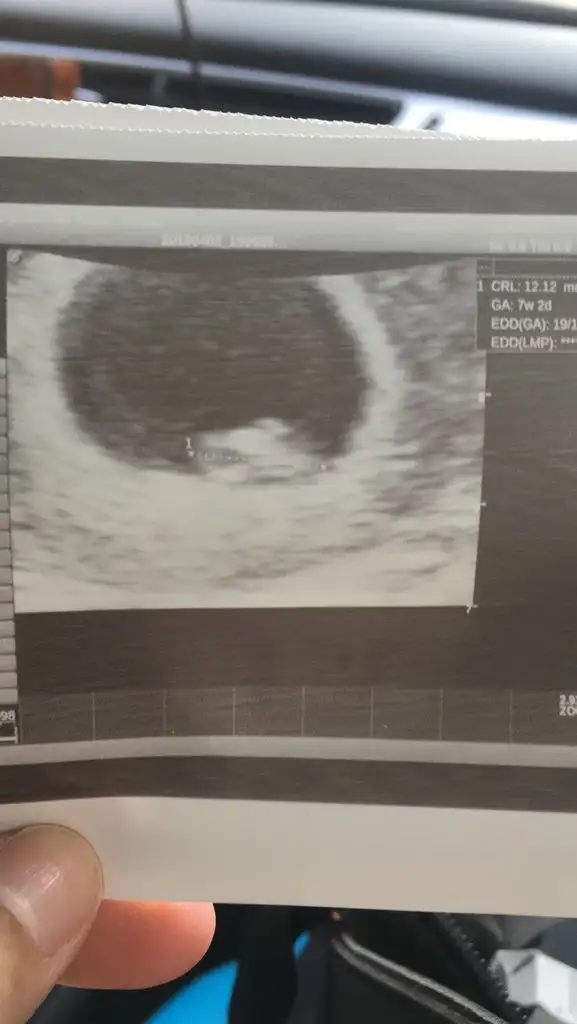

Selam kizlar bi sure uzak kaldim buraya umarim herkes iyidir 😊 dün minigimi gormeye gittik 1 cm olmus bile iste buda fotografimiz 😍